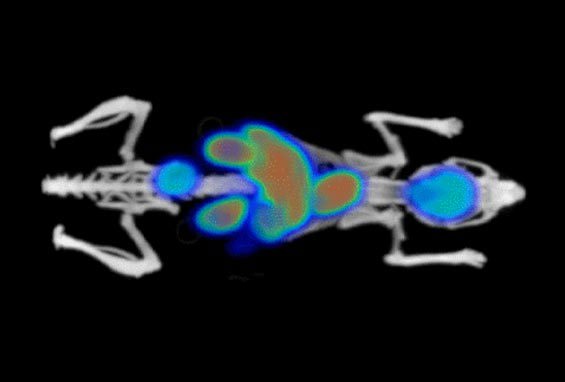

BioMouse with imaging agents Phantech anatomical model

Creating the BioMouseTM posed some challenges, such as balancing anatomical accuracy, material density control, and model versatility. The phantom needed to replicate real biological tissue and bone densities accurately while incorporating customizable voids for organs and tumors. These voids are designed to be filled with imaging agents for different modalities, including PET, SPECT, CT, and MRI. Phantech’s goal was to create a repeatable, anatomically precise model that could be used in diverse imaging environments while reliably representing biological responses.

This combination allowed the BioMouse to be used not only in CT imaging but also in nuclear medicine modalities, extending its versatility across multiple imaging types. With Stratasys Direct’s manufacturing capabilities, Phantech could produce BioMouseTM models with distinct voids for organs like the brain, heart, liver, and kidneys. Each model could then be filled with imaging agents tailored to the modality, providing the adaptability needed for cutting-edge calibration and imaging tests.

With help from Stratasys Direct, Phantech ramped up production of the BioMouse to meet growing demand, delivering a model known for its anatomical accuracy and versatility in medical imaging calibration. This benchmark device empowers researchers and imaging scientists to perform consistent, high-quality tests without relying on live specimens. The BioMouse is instrumental in optimizing imaging algorithms, validating radio-pharmaceuticals, and advancing important research.